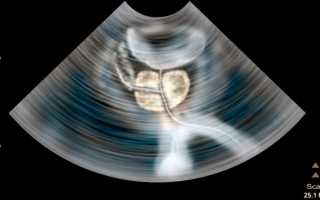

Если результаты анализов неудовлетворительные: повышенное СОЭ (скорость оседания эритроцитов), высокое содержание лейкоцитов, врач может направить пациента на УЗИ исследование и томографию.